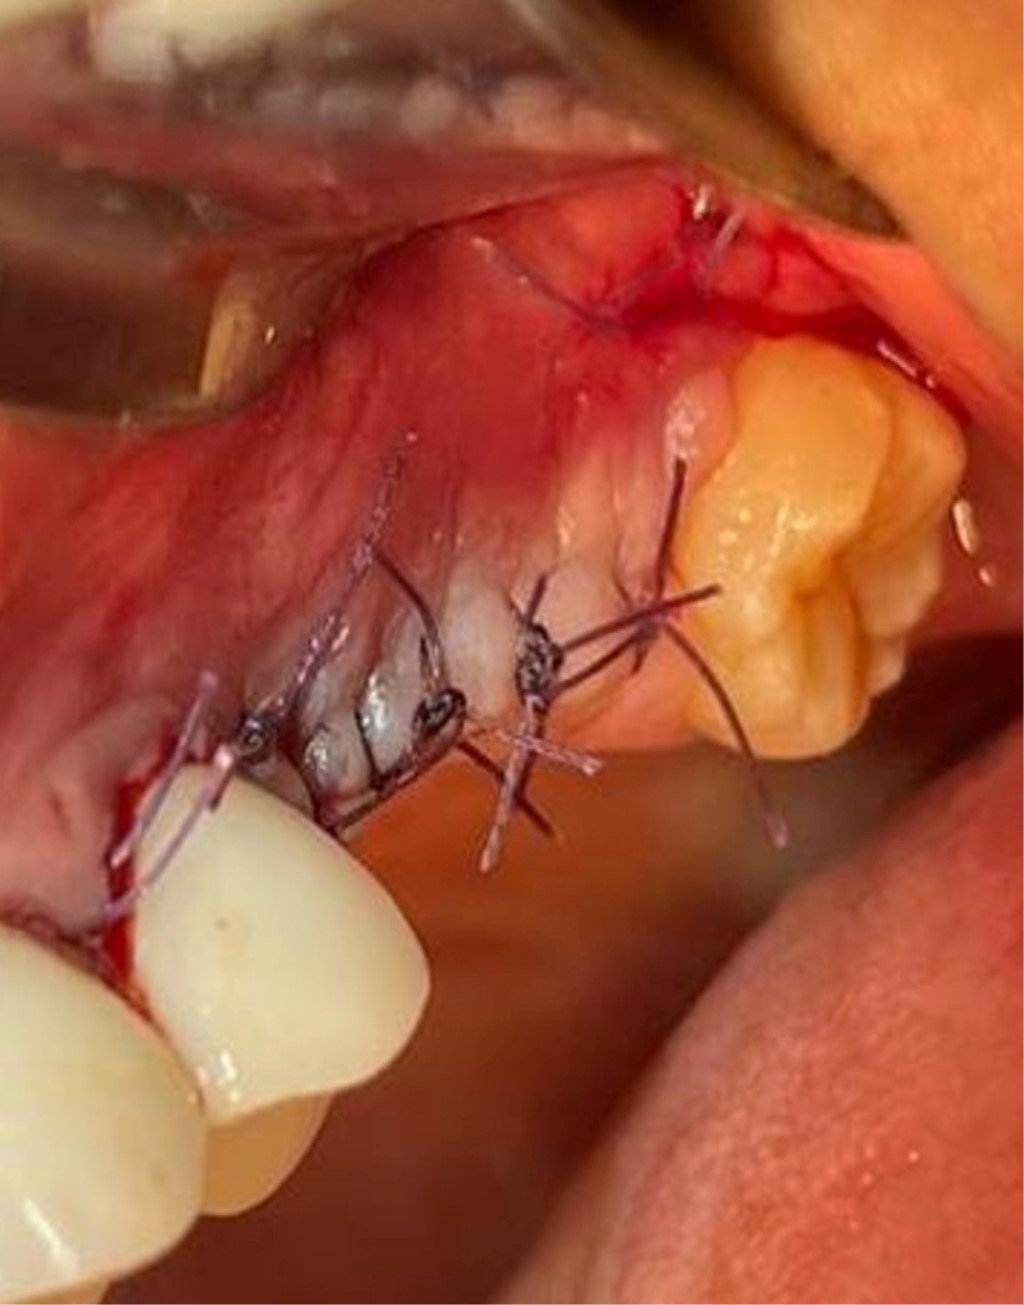

Figure 2